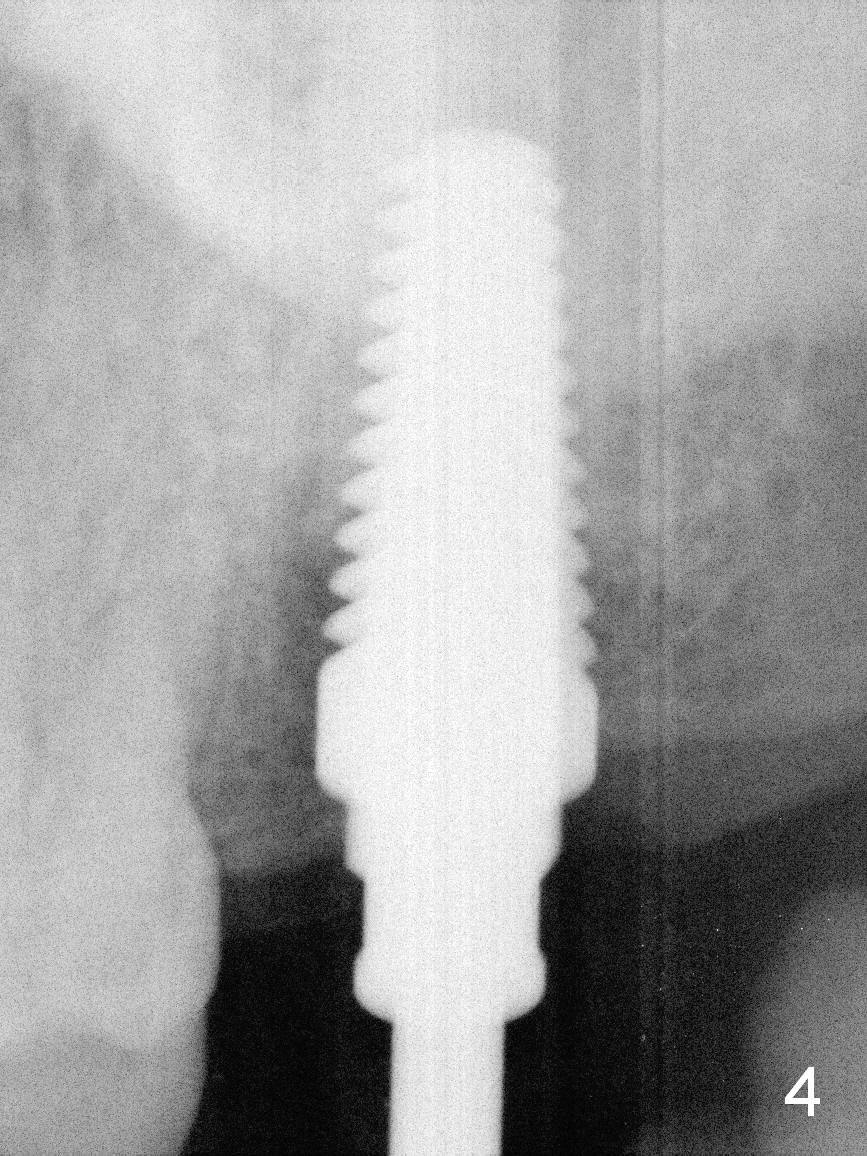

A 50-year-old man (TK) had sign & symptom of crack tooth at #15 (Fig.1) and chose to have root canal therapy done by a specialist. One month later, he returns for crown; exam reveals a crack line mesiodistally (Fig.2). The patient agrees to have immediate implant (Fig.3 design: 6x14 mm). The buccal roots fracture upon luxation. Osteotomy starts in the septum with a 2 mm pilot drill and deviates to the palatal socket, followed by 2, 3, 4 mm tapered osteotomes. A series of taps are placed: 6x17 mm one achieves stability (Fig.4). When the latter is removed, there is no sign of sinus air leakage. A 6x14 mm implant (Fig.5 I) and a 5x3 mm abutment (A) are placed. After abutment height adjustment, an immediate provisional is fabricated. Allograft with Osteogen is placed in the remaining sockets and gaps (Fig.6 *). Fig.7 shows the inner side of the provisional with double arrows indicating the dimension of the abutment, whereas arrowheads the dimension of the socket buccopalatally. When the provisional is cemented (Fig.8 P), it completely seals the socket. As long as the provisional stays, bone graft will not be lost.